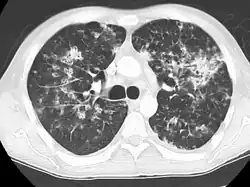

A case of miliary tuberculosis in an 82-year-old woman:

CT, 16 days after onset, showing extensive pulmonary parenchymal involvement consisting of irregular septal thickenings with ground-glass areas and centrilobular nodules with a peri-lymphatic distribution -